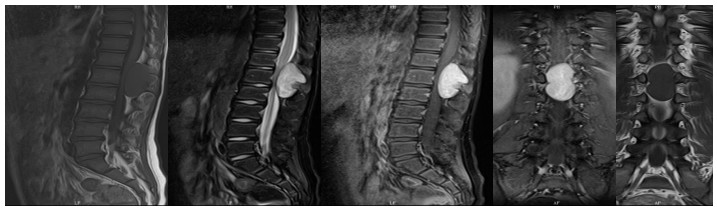

59歲鄒阿姨術(shù)前胸椎MRI檢查

10歲小孩術(shù)前增強MR